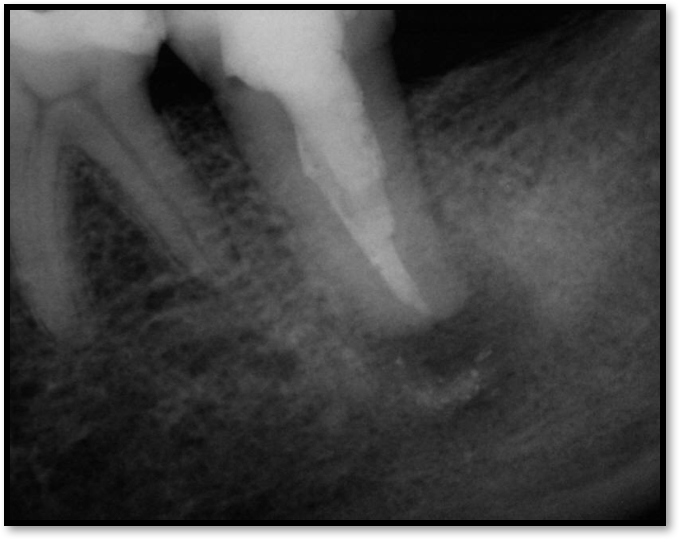

If a tooth stands alone, greater forces will be placed on it because it has no adjacent teeth to provide support. This situation will affect the decision-making process for placing a post. Figure 3 shows a tooth that was on an island and would be having three implants placed in front of it. The tooth would take a much greater beating than another tooth that had support proximally. Even though it had a good root canal, the clinician would need to account for whether the tooth would last until the implants integrated. Figure 4 shows a case that would quickly proceed to implants. The patient had a less-than-ideal bridge for over a decade, with decent endodontics and functionality. There was also an overhang on the premolar. The post was not ideal in this case because there was one distal canal and not all the gutta-percha was removed from it. An intimate fit should be the goal with the post and the walls. Whether using a threaded or non-threaded post, there should not be excess gutta-percha because it is not as solid as the tooth and will lead to greater movement. That movement on the tooth and bridge will create too much force and result in demise.

Fig 4. Case that quickly would proceed to implants.

Figure 4